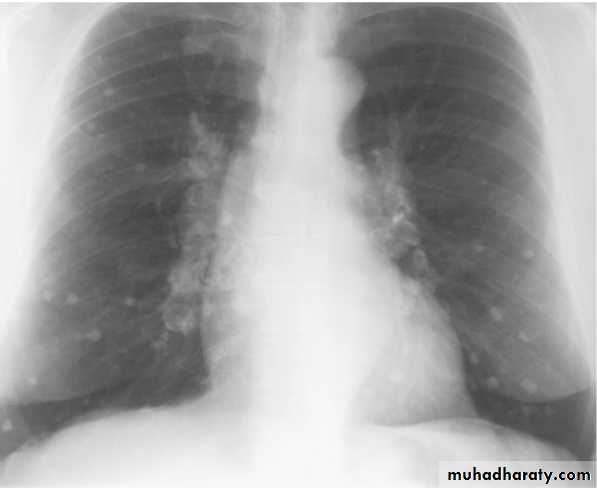

Differential diagnosis of multiple spherical lesions:

1 - Metastasis.

2-Hydatid cyst.

3- Sarcoidosis.

4- Rheumatoid nodules.

5 – pneumoconiosis

6- Histoplasmosis

Chest X-ray shows radio-opaque (white) nodular lesion in the right mid-lung field.

Dx:x chicken pox , Histoplasmosis (calcified granuloma).